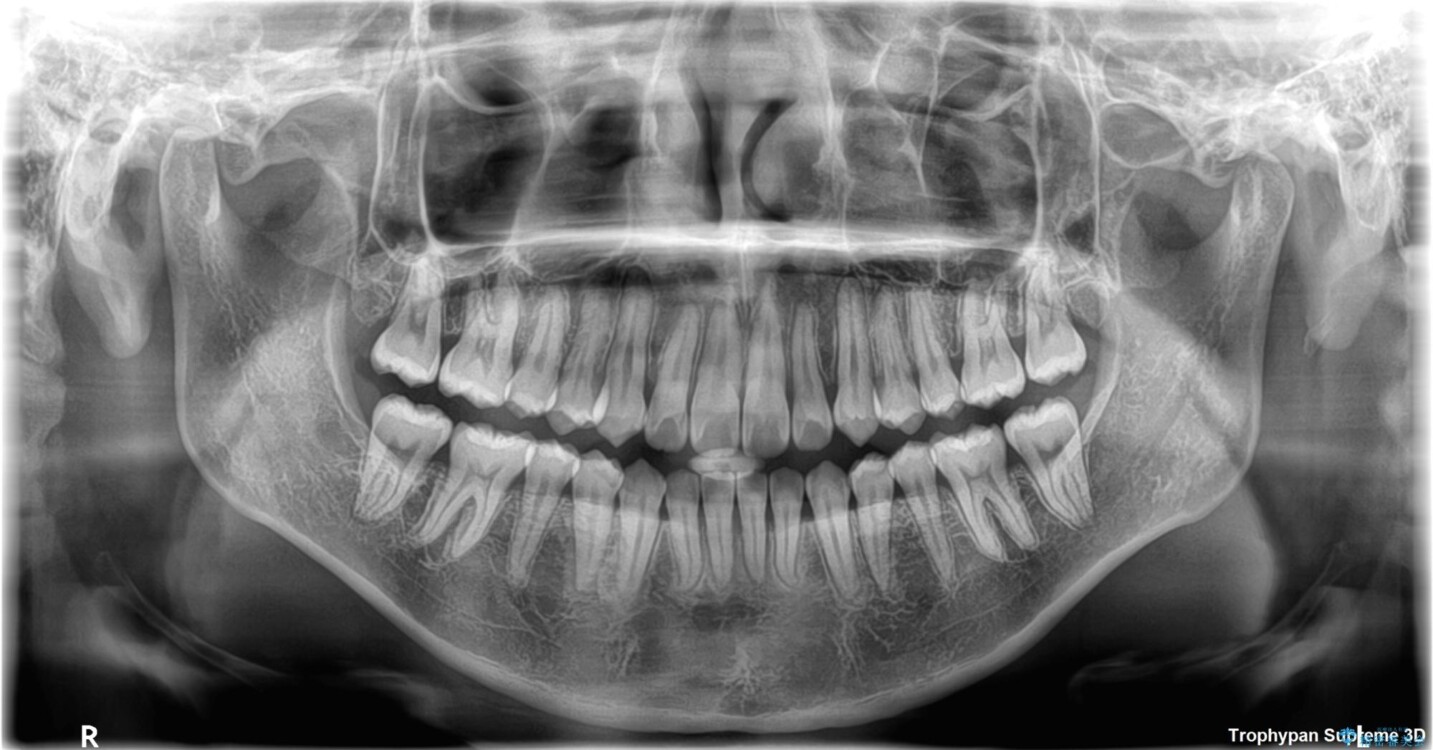

「前歯のデコボコ(叢生)をきれいに整えたい」とのことでご来院されました。

マウスピース矯正も検討されていましたが、「装着時間の自己管理が難しそう」「なるべく早く治療を終えたい」とのご希望から、ワイヤー矯正を選択されました。

目立ちにくさと費用のバランスを考慮し、プラスチックブラケット+メタルワイヤーを採用。日常生活でも装置の存在感を気にせずお過ごしいただけます。

患者様の協力もあり、およそ1年間で治療を完了。スムーズな歯の移動を実現しました。

上下の正中(真ん中のライン)もずれることなく、バランスの取れた美しい歯並びに。笑顔に自信を持てる仕上がりとなりました。